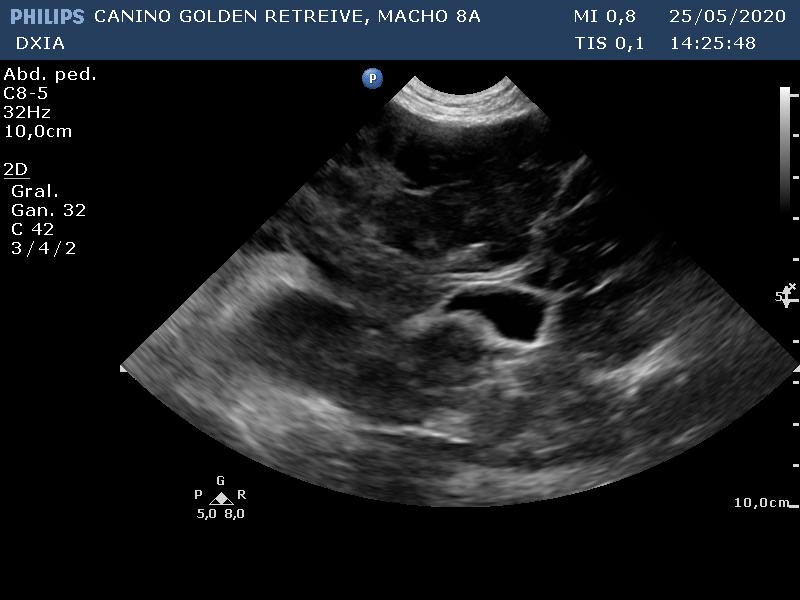

SCOTT_CANINO GOLDEN RETREIVE-desenlace01

SCOTT_CANINO GOLDEN RETREIVE-desenlace02

SCOTT_CANINO GOLDEN RETREIVE-desenlace03

En el ecocardio, gráficamente no hay alteraciones. En la ecografía abdominal, hay gran distensión por presencia de líquido libre abdominal y alteración de todo el parenquima hepático (patrón modular marcado) con hepatomegalia.